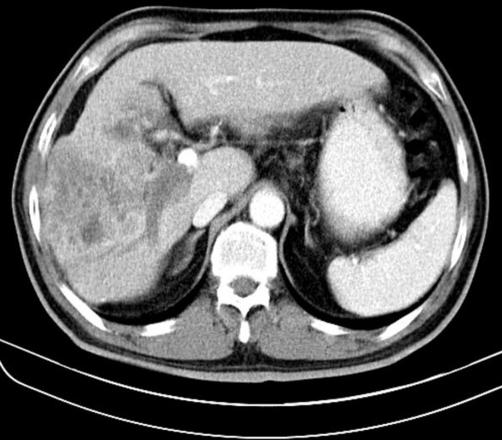

We present a unique case of hepatocellular carcinoma with mucin-producing gland formation. A 53-year-old man with hepatitis B infection presented with weight loss for the past month. Computed tomography demonstrated a 10 x 9.8 cm mass in the right hepatic lobe accompanied by cirrhotic changes in the hepatic parenchyma. Right hepatectomy was performed, and the tumor cut surface showed a poorly-circumscribed, white to pink tumor with numerous nodules and extensive necrosis. Microscopically, the tumor was composed of thick trabeculae and large, irregularly-shaped islands, both of which were filled with pleomorphic eosinophilic hepatoid cells or gland-forming columnar cells with mucin production. Those cells were immunoreactive for cytokeratin 19 in both the trabeculae and the glands. In some tumor cells, limited immunoreactivity for cytokeratin 7, epithelial membrane antigen and carcinoembryonic antigen was noted. The cells forming thick trabeculae were focally positive for hepatocyte paraffin 1 and alpha-fetoprotein. We suggest that this tumor shows bidirectional differentiation into hepatocytes and cholangiocytes, supporting the concepts that human hepatocarcinogenesis can be based on transformation of progenitor cells which can imply divergent differentiation.

摘要

我们报告一例独特的伴有黏液生成性腺形成的肝细胞癌病例。一名53岁的乙型肝炎感染男性患者,出现了过去一个月体重减轻的症状。计算机断层扫描显示右肝叶有一个10×9.8厘米的肿块,肝实质伴有肝硬化改变。进行了右肝切除术,肿瘤切面显示边界不清,呈白色至粉红色,有许多结节和广泛坏死。显微镜下,肿瘤由粗大的小梁和大的、不规则形状的岛状结构组成,两者均充满多形性嗜酸性肝样细胞或产生黏液的腺形成柱状细胞。这些细胞在小梁和腺体内对细胞角蛋白19均呈免疫反应阳性。在一些肿瘤细胞中,观察到对细胞角蛋白7、上皮膜抗原和癌胚抗原有有限的免疫反应。形成粗大小梁的细胞对肝细胞石蜡1和甲胎蛋白呈局灶性阳性。我们认为该肿瘤表现出向肝细胞和胆管细胞的双向分化,支持人类肝癌发生可基于祖细胞转化这一观点,而祖细胞转化可能意味着不同的分化。